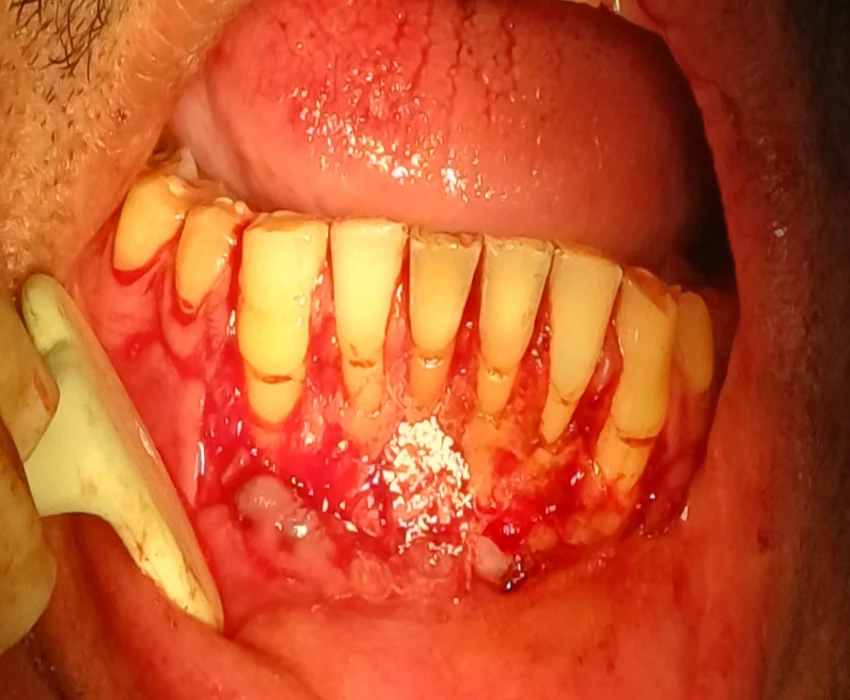

Treatment- non-surgical endodontic treatment was initiated and following obturation of the canal a periapical surgery including curettage, apicectomy, and retrograde filling with MTA was performed.